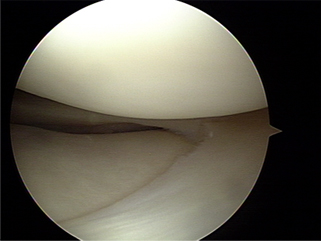

정상 관절내 연골 사진